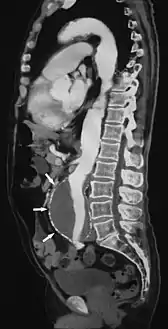

![]() مقطع متعدد الطبقات لأم الدم الأبهرية البطنية (مؤشر عليها بالأسهم) | |